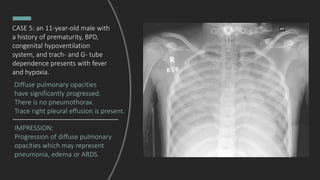

CASE 5: an 11-year-old male with

a history of prematurity, BPD,

congenital hypoventilation

system, and trach- and G- tube

dependence presents with fever

and hypoxia.

IMPRESSION:

Progression of diffuse pulmonary

opacities which may represent

pneumonia, edema or ARDS.

Diffuse pulmonary opacities

have significantly progressed.

There is no pneumothorax.

Trace right pleural effusion is present.